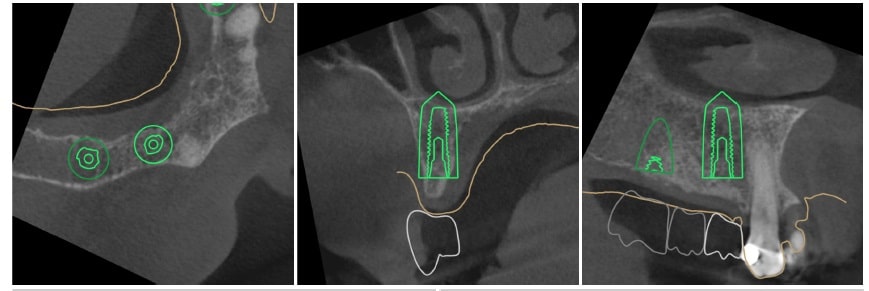

Using the 3D images in special planning software, the Dentist maps out the exact position and angle of insertion of each implant. They take care to place implants where they will be stable and in the best position to support the replacement teeth. They will also plan out any bone grafting (if needed) to ensure the implants have strong bone support.

Surgical Guides to Ensure Accuracy of Placement

We manufacture and use a surgical guide to aid in efficient, accurate and minimally invasive implant placement. A surgical guide is a template that fits over the dental arch and marks exactly where and at what angle to place each implant.